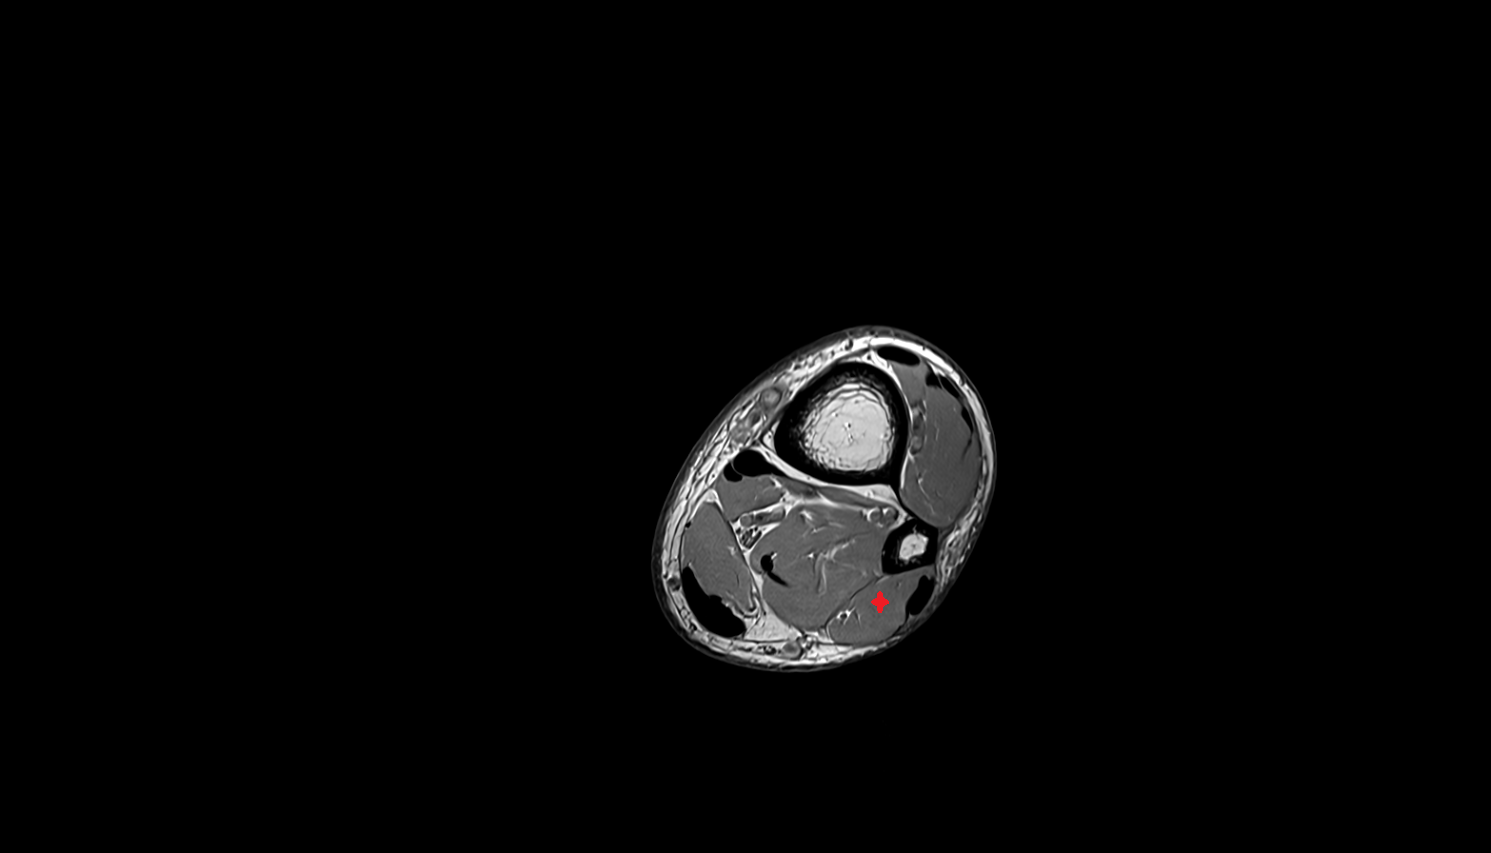

- Ankle joint

- Talus

- Calcaneus

- Medial malleolus

- Lateral malleolus